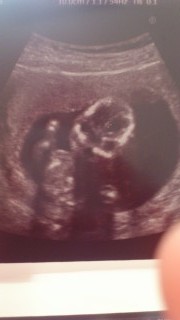

手足も長いし、指もちャんと5本見えるね♪と先生から言われました!この日は体育座りをしていてなかなか性別を教えてくれませんでした-。可愛すぎてもぉパパもベタ惚れです★

横顔と身体☆

こっちを向いている写真です(^_^)